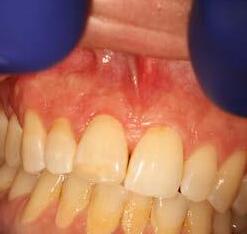

This is not a “Terminal Dentition”. It is interesting to see the increase in patients being advised that Periodontitis is not treatable or that treatment is somehow expensive and ongoing maintenance is difficult/unachievable. These patients are usually advised to receive implant treatment as an alternative.

This patient first presented in 2016 at the age of 33 years. He was a former smoker (quit two years prior to the initial presentation). He presented with generalised deep pocketing and advanced loss of attachment.

Radiographic assessment showed generalised moderate to advanced bone loss with most teeth showing bone loss to more than 50% of the root length. Given the established loss of attachment in relation to his relatively young age, this patient was diagnosed with generalised aggressive periodontitis. According to the 2017 Classification of Periodontal Disease, he would be Stage III, Grade C Periodontitis.

The patient was managed with non-surgical periodontal debridement. Two months later, he presented with an encouraging reduction in periodontal probing depth (PPD). There were 85% sites with PPD 1-3mm, 15% sites with PPD 4-5mm and no sites with residual PPD > 6mm. The patient showed excellent plaque control measures and his bleeding on probing score was 1%. The patient has been placed on a six-monthly periodontal maintenance program with the periodontist. He also sees his general dentist once annually. The OPG images dated 2016 and

2023 show stable bone levels with no evidence of further bone loss.

The patient had orthodontic treatment between 2018-2020 to address the flaring and spacing of his teeth, which was a cosmetic concern to him (orthodontic treatment done by Dr Frank Furfaro). Long-term evidence shows that we, as dental clinicians, are not accurate at determining the prognosis of periodontally compromised teeth (McGuire 1996). We may also be hasty at labelling such teeth as “hopeless”. The threshold at which we

decide to extract teeth due to periodontal disease may be too low (Splieth 2002). There is no evidence on the other hand that dental implants have longer survival or less complications or better cost compared to periodontally treated teeth.